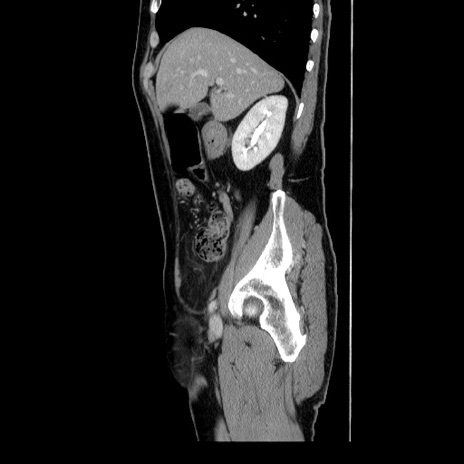

横断像

【症例】60歳代 男性

【主訴】右鼠径部膨隆

【現病歴】1年程前より右鼠径部膨隆あり。自己にて還納可能だったため放置していた。3時間前より右鼠径部の脱出を認め、還納困難となり受診。

【身体所見】右鼠径部に小児頭大の膨隆あり。弾性硬であり、用手還納は困難。左鼠径部にも膨隆を認める。脱出はなし。